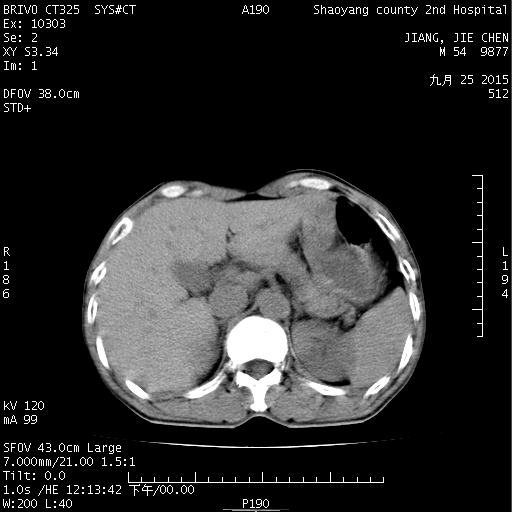

CT51164:看看是结石还是静脉石

看看是结石还是静脉石

考虑左侧输尿管末端小结石;建议行CTU检查。

盆腔左侧似见点状高密度影,左侧输尿管远端小结石可疑。

左侧输尿管末端小结石可能

未见异常。